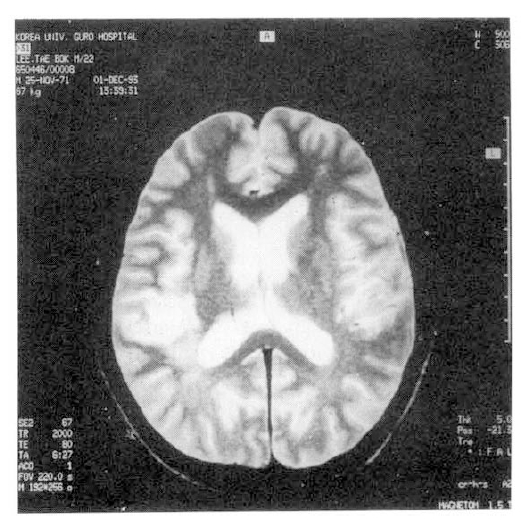

On admission, white blood cell count was 6.4×103/mm3 with left shift (seg.neut. 55%, band neut. 32%, lymph. 10%, mono. 3%). Hematocrit was 15%, hemoglobin 5.5gm/dl, and the reticulocyte count was 3.5%. The erythrocyte sedimentation rate was elevated at 23 mm/h (Westergren). The direct Coomb’s test was positive. Review of the peripheral blood smear showed unremarkable red cell morphology. Urinalysis showed 100 mg/dl protein, 5–7 white cells and many red cell. The urine hemosiderin and hemoglobin were negative. Renal function evaluation revealed blood urea nitrogen 26 mg/dl, creatinine 1.5 mg/dl, 24 hr urine protein 3.4 gm/day, and the creatinine clearance was 55 ml/dl. The serum electrolyte were normal, except for potassium of 3.2 mmol/I. The AST was 34 IU/I, ALT 42 IU/I, alkaline phosphatase 48 IU/I, total bilirubin 0.7 mg/dl, total protein 5.8 gm/dl and albumin 2.7gm/dl. The platelets were 22×103/ml, PT 10.7/100 (sec/%) and aPTT 34/28(sec, patient/control). Rheumatoid factor was negative and ANA was positive (speckled pattern, titer 1:160). The anti-dsDNA antibody was above 100 U/ml (N; 0–25 U/ml). The anti-Sm, anti-RNP, anti-Ro and anti-La antibodies were all positive. Complement levels were decreased at C3 26.5 mg/dl (N; 52.6∼120 mg/dl), C4 8.0 mg/dl (N; 20.5∼49 mg/dl). Anticardiolipin antibodies (aCL) were positive for both IgG and IgM (by ELISA) and VDRL was reactive, TPHA nonreactive and FTA-Abs negative. The levels of protein C, protein S and antithrombin III were within normal limits. Plain radiology of chest was normal. Abdominal ultrasonography revealed moderate amount of ascites, splenomegaly and diffusely increased renal parenchymal echogenicity. Magnetic resonance imaging (MRI) brain scan revealed ischemia in right parieto-temporal white matter (Fig. 1). EKG showed sinus bradycardia and low voltage on limb leads. Echocardiography confirmed mild pericardial effusion without vegetation and thrombus.

Fig. 1.

Axial, T2-weighted spin echo MRI scan of brain shows area of high signal intensity in right parieto-temporal white matter.